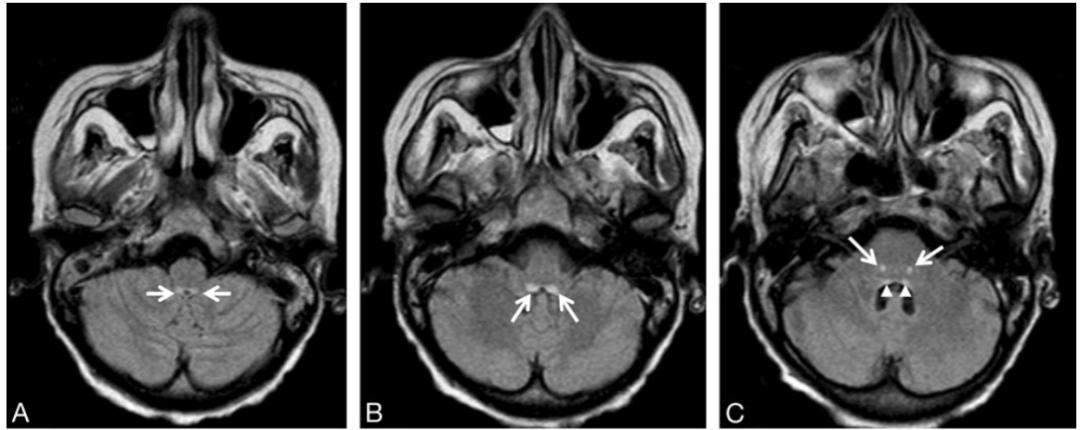

男,54歲,白血病病史。臨床表現(xiàn)為意識障礙、共濟失調。Flair示高信號位于雙側舌下神經(jīng)核(A)、前庭神經(jīng)內側核(B)、面神經(jīng)核(長箭頭)和展神經(jīng)核(短箭頭)(C)、中腦頂蓋和導水管周圍灰質(D)、乳頭體(E)、下丘腦和第三腦室周(F)。